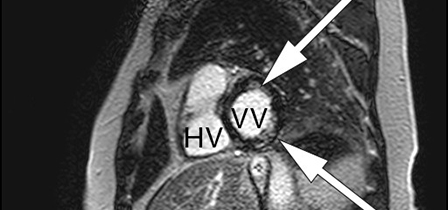

Som ved alle andre undersøkelser er sensitivitet og spesifisitet avhengig av sykdommens prevalens, undersøkelsesmetode og legen som vurderer resultatet av undersøkelsen. Ved MR cor kan man oppdage både inflammatoriske og fibrotiske forandringer som er assosiert med kardial sarkoidose (fig 1–3) (7).

Den aktive, inflammatoriske sykdomsfasen kjennetegnes av økt gadoliniumkontrastopptak ved tidlig undersøkelse og veggfortykkelse som oppstår sekundært til granulomatøs infiltrasjon og ødem (6, 7). Dersom pasientene har utviklet fibrotiske forandringer, vil MR-undersøkelsen vise kontrastopptak ved sen undersøkelse, kalt sen kontrastutvasking (4). Fibrotiske forandringer ved MR-undersøkelse kan være en prognostisk markør som er assosiert med ventrikulære arytmier og mortalitet (4). Fibrosen forekommer som regel ikke i klassiske arterielle forsyningsområder, i motsetning til ved aterosklerotisk hjertesykdom (5). I tillegg vil kontrastoppladningen ved et hjerteinfarkt alltid involvere subendokard (med varierende grad av transmuralitet), mens ved kardial sarkoidose kan kontrastoppladningen forekomme i alle deler av myokard (6).